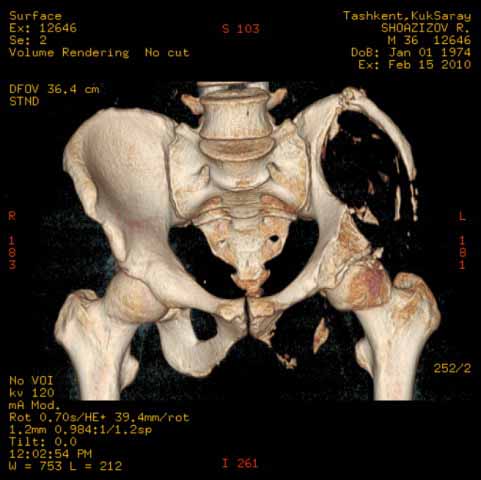

И 2010 год

Также структуру поражения кости можно увидеть на обычных рентгенограммах таза или Компьютерно-Томографических срезах. Трехмерные снимки, кроме красивой картины, не добавляют информации, и самым главным информативным является МРТ, которая покажет структуру ячеек.